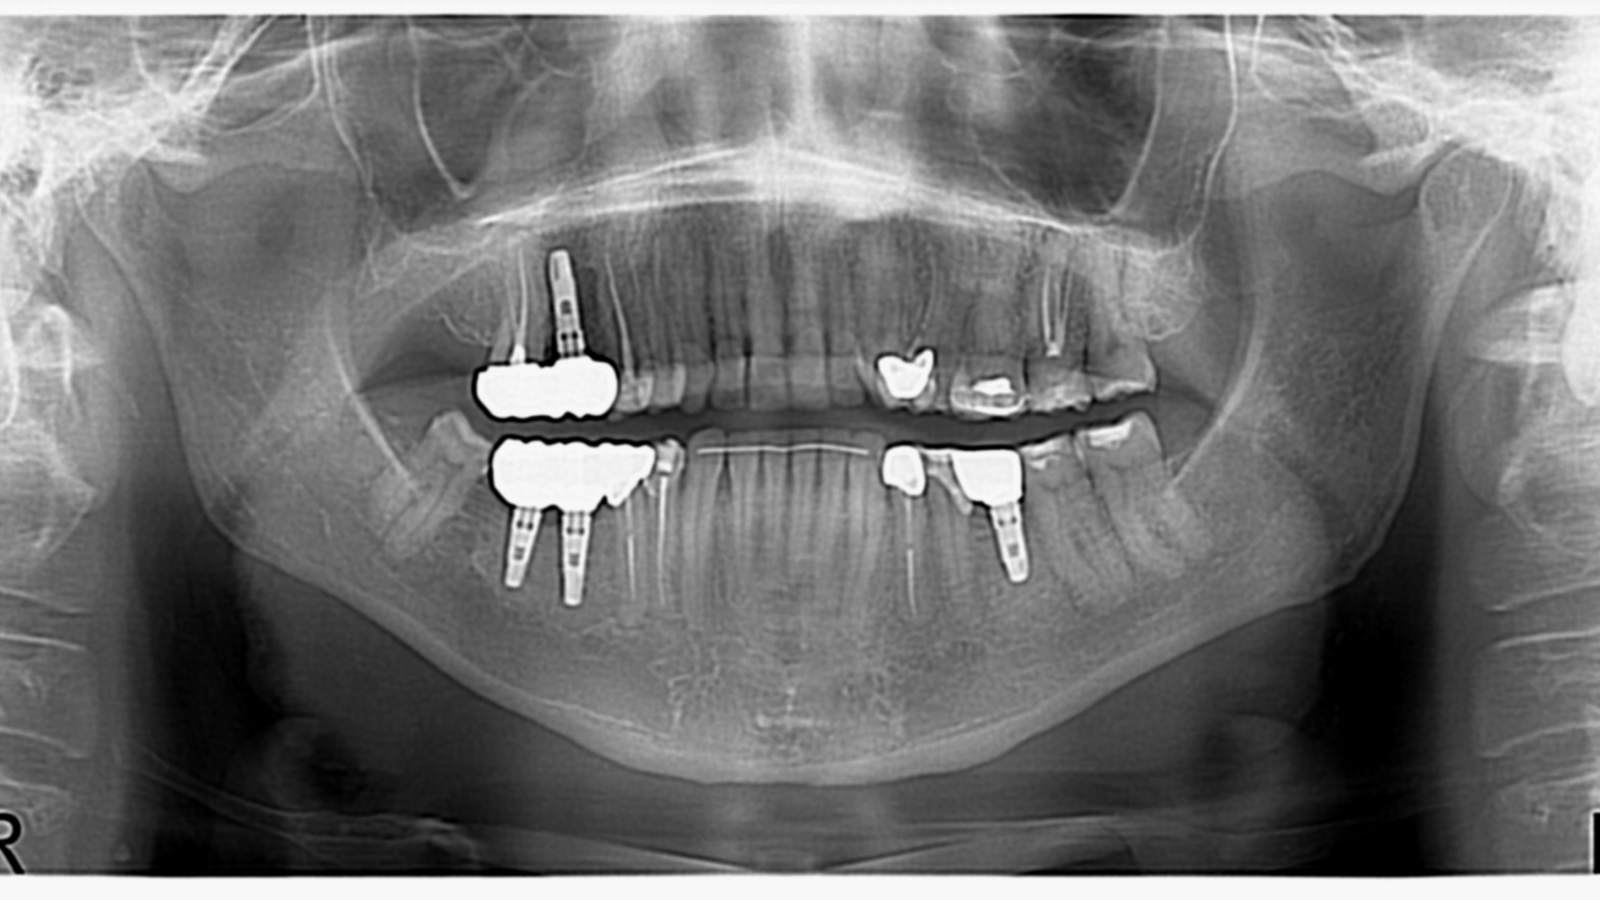

Réhabilitation complète avec mise en charge immédiate (4 implants bas / 6 implants haut)

Le patient se présente avec des dents qui bougent, en haut et en bas.

Nous avons commencé par la mâchoire inférieure avec 4 implants et une mise en charge immédiate.

Trois mois après, le haut a été fait avec le même principe avec 6 implants.

Cette fois-ci, il existait un déficit osseux, résolu par une technique d’expansion sans avoir recours à la greffe d’os.

Les prothèses réalisées sont vissées, ce qui permet de les enlever, les nettoyer une fois par an, ou résoudre n’importe quel problème.